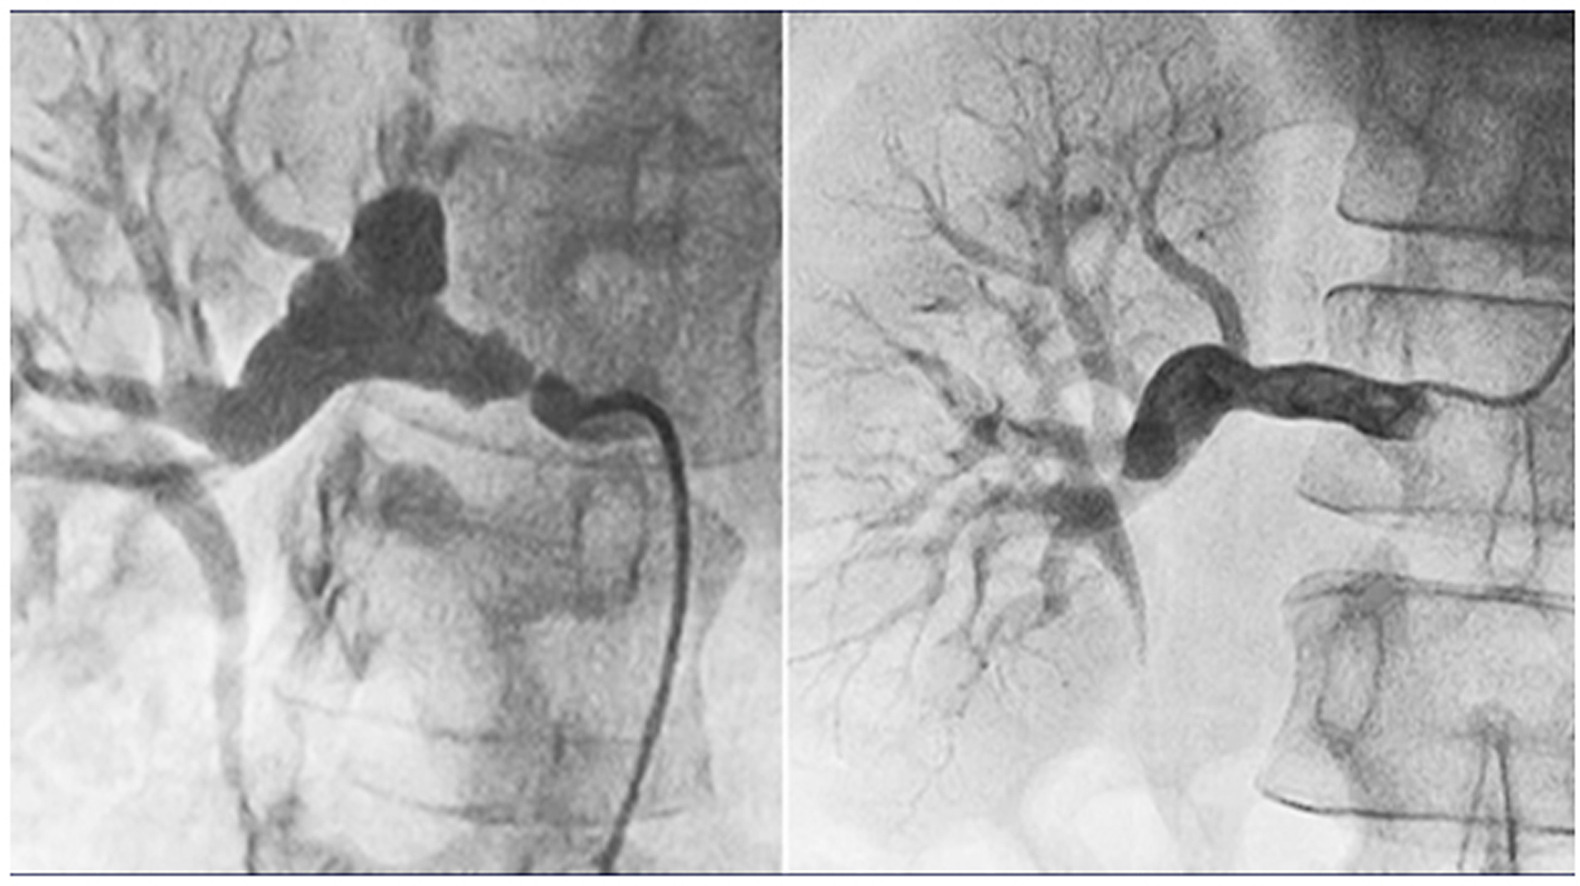

Figure

Digital subtraction angiograms showing pretreatment (left) renal artery stenosis and aneurysm, and post-treatment (right) improvement in the aneurysm size after successful angioplasty.

Fibromuscular dysplasia (FMD) is an idiopathic, segmental, nonatherosclerotic, and noninflammatory arterial disease, which most commonly affects the renal and internal carotid arteries. Endovascular treatment for RAS and RAA in patients with FMD is limited, and the prognosis of RAA when RAS is treated remains unclear.

The success rate of RAS-specific endovascular therapy was 100%, and the mean degree of stenosis decreased from 86.4% -11.9 to 12.6% -5.7%. The maximum diameter of all RAAs and SRAAs decreased significantly during a mean of 4.2 years, and the maximum diameter of non-SRAAs did not change. In the 19 patients with FMD, the systolic and diastolic blood pressures decreased, the number of antihypertensive medications decreased, and the serum creatinine level remained stable. The primary patency rates of PTRA and stent implantation were 89.5% and 100%, respectively.